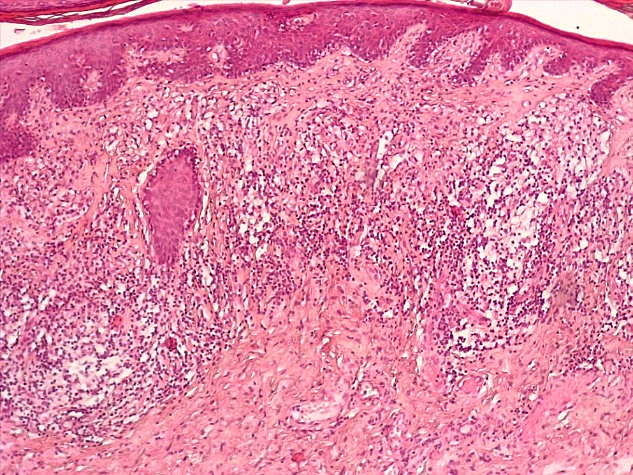

При морфологическом исследовании биоптатов вульвы пациенток с атрофическим вариантом течения СЛВ наибольшие изменения наблюдались со стороны эпидермиса и поверхностных слоев дермы. В эпидермисе отмечалась резкая атрофия клеток многослойного плоского эпителия (МПЭ) с участками повышенного ороговения (гиперкератоза и паракератоза), в некоторых случаях были выявлены участки фибриноидного некроза с окружающей лейкоцитарной клеточной инфильтрацией (рис. 1), указывающие на наличие очагов острого язвенного повреждения эпидермиса на фоне дистрофических и регрессивных изменений многослойного плоского эпителия. При этом количество клеточных слоев эпидермиса было уменьшено в среднем до 3–4 с избыточным образованием роговых чешуек в поверхностных слоях, а количество базальных клеток эпидермиса в 1 мкм не превышало 10, что свидетельствовало об атрофии резервного слоя эпидермиса (рис. 2).

Рис. 1. Атрофический вариант течения СЛ вульвы. Участок фибриноидного некроза с лейкоцитарной инфильтрацией многослойного плоского эпителия с развитием паракератоза, дискератоза. Развитие плотной волокнистой соединительной ткани в поверхностных слоях дермы с умеренной лимфо-гистиоцитарной инфильтрацией (окраска гематоксилином-эозином, х100)

Fig. 1. Atrophic variant of the course of the vulva SL. A site of fibrinoid necrosis with leukocyte infiltration of multilayer squamous epithelium with the development of parakeratosis, dyskeratosis Development of dense fibrous connective tissue in the superficial layers of the dermis with moderate